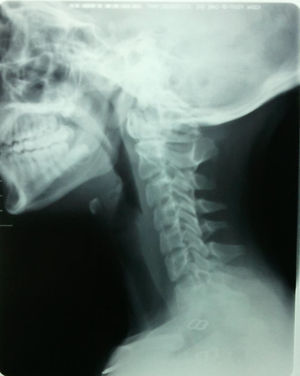

Ante el antecedente del traumatismo se solicita una radiografía de columna cervical en 2 proyecciones anteroposterior y lateral, donde se observa rectificación cervical e imágenes no definidas a nivel del cuerpo de los últimos arcos vertebrales, por lo que se solicita una tomografía axial computarizada (TAC) cervical.

La TAC cervical informa de la existencia de defectos de fusión de los arcos anterior y posterior del atlas con presencia de bordes escleróticos en el arco anterior. Se aprecia la existencia de una hemivértebra derecha C7 (cervical 7) que condiciona escoliosis de la columna cervical. Rectificación de la columna cervical. No se observan líneas de fractura agudas, ni afectación del canal medular.

En el caso que presentamos, si no se hubiera valorado la radiografía anteroposterior habría pasado desapercibida la malformación a nivel del cuerpo vertebral de la C7, así como en la radiografía lateral el defecto de fusión a nivel del atlas; por tanto es necesaria una sistemática en la valoración de las radiografías de columna cervical aunque la clínica no sea muy llamativa (figs. 1 y 2).